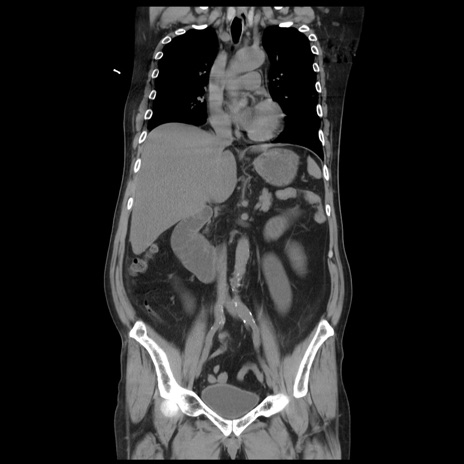

症例20(冠状断像)

【症例】 60歳代男性

【主訴】 腹部膨満、嘔吐

【現病歴】5日前頃より倦怠感を認め食事量減少し4日前の朝嘔吐、食事摂取困難となった。 3日前近医受診し点滴施行され整腸剤などを処方された。 当日他院を受診し、腹部膨満著明、炎症反応の上昇(CRP10.8、WBC11200)あり、紹介受診となる。

【身体所見】 意識JCS1 受け答えがはっきりしないBP 111/57mHg、 P 67bpm、、BT35.2°C、SpO2 97%(RA)、 腹部:膨隆、打診で鼓音あり、全体的に圧痛有り、腸蠕動音(-)、反跳痛ははっきりせず。

【データ】WBC 11400、CRP 14.20